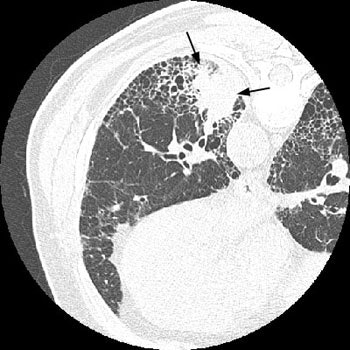

The patient below had severe interstitial lung disease. An ill-defined density was detected in the left lower lobe- a bronchogenic carcinoma was subsequently diagnosed. Patients with interstitial lung disease are at increased risk for developing bronchogenic carcinoma:CXR reveals interstitial lung disease and a soft tissue mass in the left lung:

CT scan demonstrates honeycombing and other characteristic findings of UIP. The mass could be seen arising in an area of severe honeycombing: